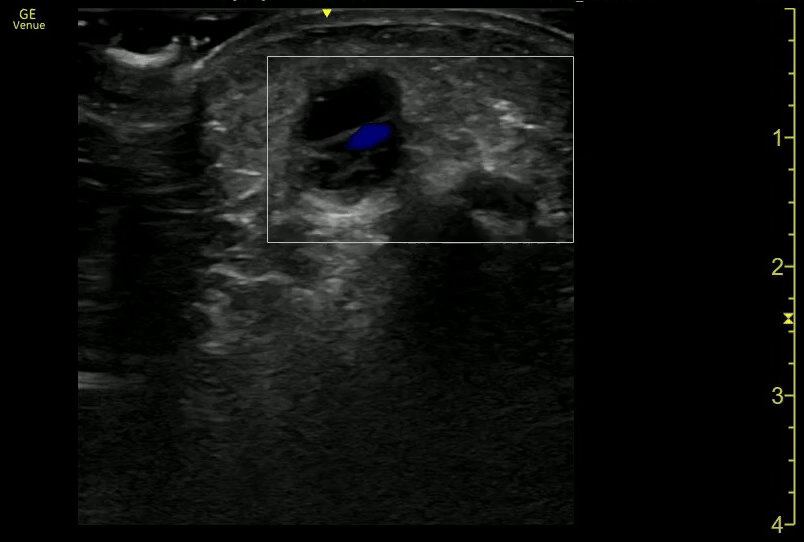

Acute Cholecystitis w Impacted Stone